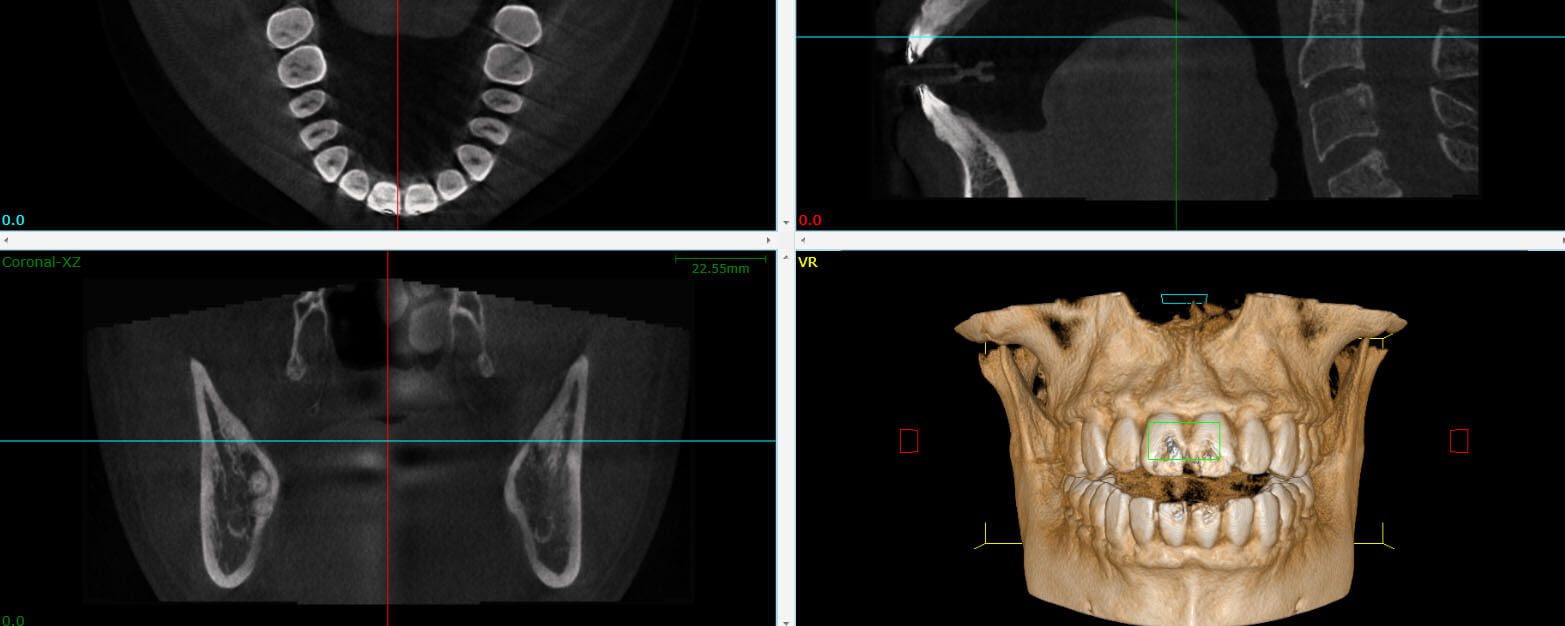

A cone beam CT creates a 3D view and cross-sections of the target area. The information it provides is critical for a number of situations. Our office utilizes this technology to aid in performing complex root canals or to search for the source of pain, infection or identified potential cracks. CBCT gives us the information we need about your condition before a dental procedure. It is not required for every case and is only taken when necessary.

A cone beam CT circles the head, which overlaps each image or slice, leaving no gaps. The radiation is also much weaker. The most radiation hits the area of interest, which is where the images overlap to construct the 3D model. This is how CBCT is able to provide a more complete image with less radiation exposure.